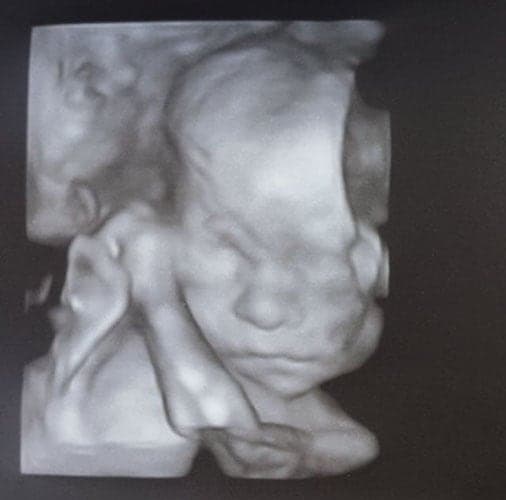

Ultraschallbilder aus dem 3. Trimester (29. bis 40. SSW)

Im dritten Trimester der Schwangerschaft ist das Baby so groß, dass es nicht mehr komplett auf ein Ultraschallbild passt. Nun kann man wunderbare 3D-Ultraschalle des Gesichts machen. In diesem Semester nehmen die Babys nochmal rasant zu und wer Glück hat, kann auf seinem Ultraschall schon erste Gesichtszüge erkennen.

Was genau man auf einem Ultraschallbild erkennen kann, hängt nicht nur von der Größe des Babys ab, sondern auch davon wie gut das Ultraschall-Gerät ist, mit dem die Aufnahme gemacht wurde. Auch auf den Ultraschallbildern hier kannst du sehen, dass die Qualität stark schwankt. In der Regel kann man gut den Kopf und RUmpf des Babys erkennen und auch die Gliedmaßen erkennt man selbst als Laie gut.

Wer sich jedoch erhofft Gesichtszüge zu erkennen, der wird oft enttäuscht. Zwar kann man beim 3D-Ultraschall schon eine Menge sehen, aber das umgebende Fruchtwasser sorgt in den allermeisten Fällen für starke Störungen.